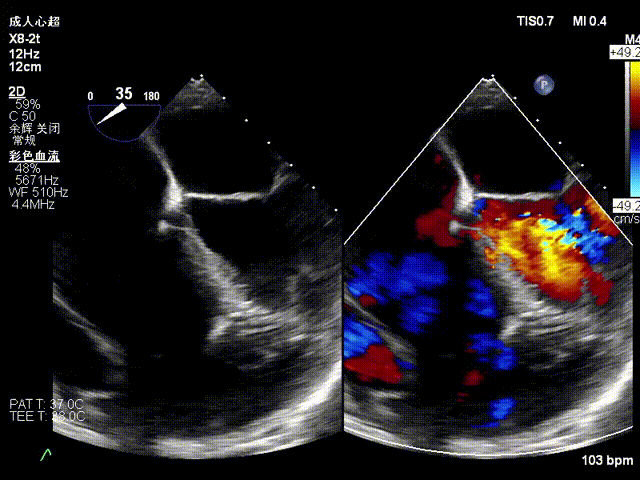

Echocardiographic Assessment:

- Massive tricuspid regurgitation (5+, mean vena contracta 14mm);

- Regurgitant orifices located at antero-septal, central, and postero-septal regions, with a significant gap at the antero-septal region (antero-septal gap 9.1mm), leaflet tethering (tethering height approximately 9mm);

- Tricuspid annular dilation (mean annulus diameter: 43mm);

Preoperative